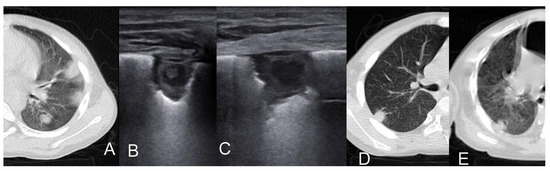

| N. of Patients | Age | Microorganism | Consolidation | Atelectasis | Cavitation | Hyper– Echoic Nodule with Hypo– Echoic Rim | Hypo– Echoic Nodule with Hyper– Echoic Rim | Pleural Effusion | B–lines | |

|---|---|---|---|---|---|---|---|---|---|---|

| Children | ||||||||||

| Trinavarat 2012 [35] | 1 | 6 weeks | Aspergillus | 1 | 1 | |||||

| (100%) | (100%) | |||||||||

| Alamdara, 2021 [36] | 6 | 5-11 yrs | 1 Mucurmicosis, 5 Aspegillus | 5 | 2 | 2 | 4 | |||

| (83%) | (33%) | (33%) | (66%) | |||||||

| Liu J., 2022 [37] | 7 | Premature newborns | 5 C. albicans, 1 C. parapsilosis, 1 Aspergillus | 7 | 2 | 2 | 7 | |||

| (100%) | (33%) | (33%) | (100%) | |||||||

| Total | 14 | 13 | 2 | 3 | 2 | 4 | 2 (14%) | 7 | ||

| (93%) | (14%) | (21%) | (14%) | (28%) | (50%) | |||||

| Adults | ||||||||||

| Tikkakoski, 1995 [38] | 4 | 49-79 yrs | 4 Aspergillus (1 A.niger, 2 A.fumigatus) | 4 | 4 | 1 (25%) | ||||

| Grabala, 2017 [39] | 1 | 41 yrs | 1 Mucurmicosis | 1 | 1 (100%) | |||||

| (100%) | ||||||||||

| Greco, 2019 [40] | 10 | Mean 44 yrs | Not specified | 10 | 4 | 4 (40%) | 8 | |||

| (100%) | (40%) | (80%) | ||||||||

| Ruby, 2021 [41] | 1 | 45 yr | 1 Aspergillus | 1 | 1 | 1 | ||||

| (100%) | (100%) | (100%) | ||||||||

| Total | 16 | 16 | 4 | 5 | 1 | 5 (31%) | 9 | |||

| (100%) | (25%) | (31%) | (6%) | (56%) | ||||||